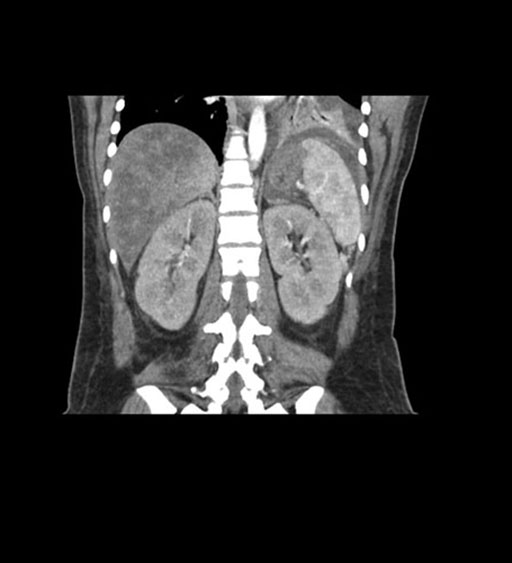

Imaging Analysis

Look through the patient's CT scan to identify any areas of concern for the necessary procedure.

Coronal Arterial

Coronal Venous